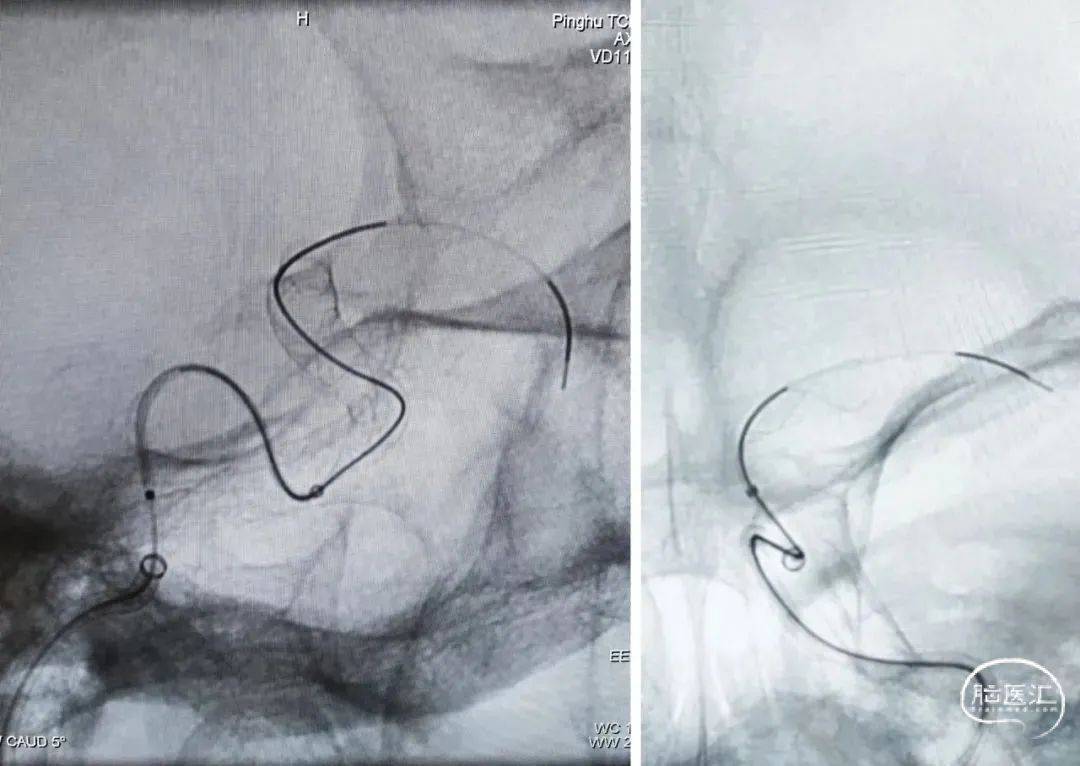

释放支架头端,远端锚定后,确认支架远端释放,贴壁良好,缓慢采用推挤方式将支架释放。

支架成功释放后,造影显示动脉瘤瘤颈支架覆盖贴壁良好,右侧颈内动脉通畅,右侧颈内动脉及分支血管显影良好,无血栓。

撤除导管,雅培血管闭合器闭合穿刺点后加压包扎压迫股动脉穿刺点,术毕,手术经过顺利,麻醉满意,术后生命体征平稳,送回病房。